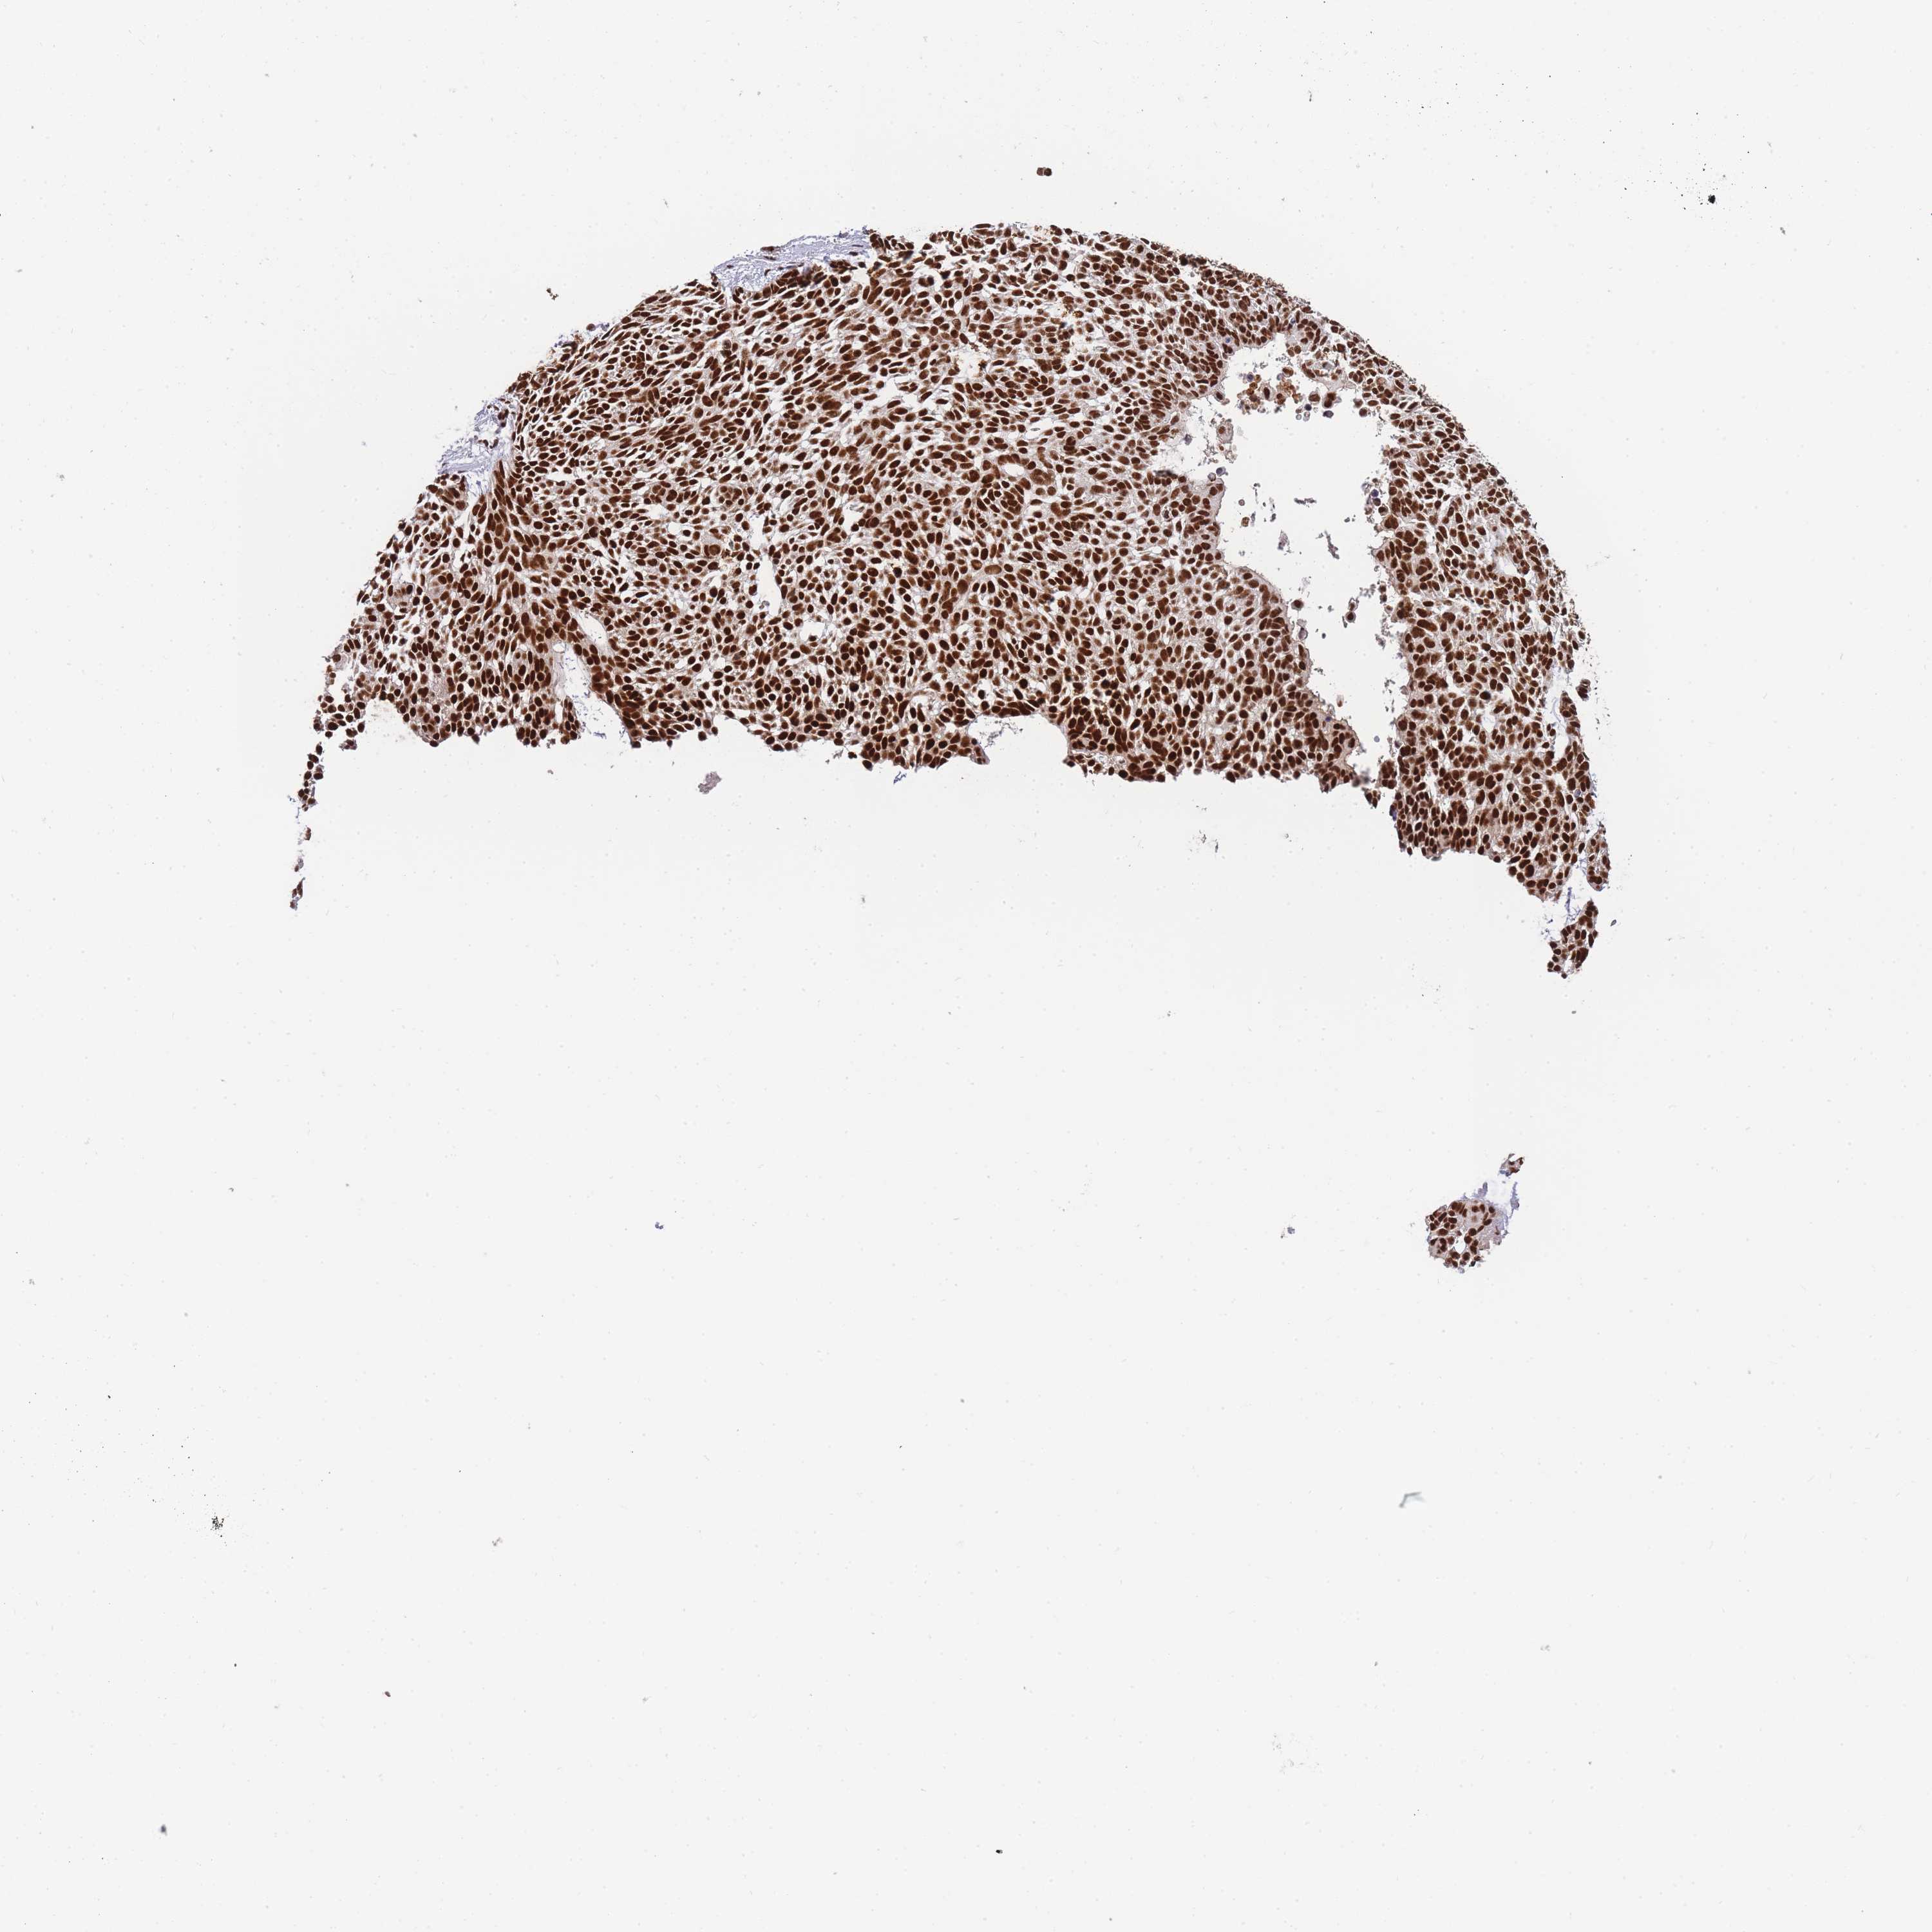

SKIN CANCER - Protein expressioni

A mouse-over function shows sample information and annotation data. Click on an image to view it in a full screen mode. Samples can be filtered based on level of antibody staining by selecting one or several of the following categories: high, medium, low and not detected. The assay and annotation is described here.

Antibody staining in the annotated cell types in the current human tissue is reported as not detected, low, medium, or high, based on conventional immunohistochemistry profiling in selected tissues. This score is based on the combination of the staining intensity and fraction of stained cells.

Each image is clickable and will lead to virtual microscopy that enables deeper exploration of all samples and also displays staining intensity scores, fraction scores and subcellular localization as well as patient and tissue information for each sample.

Antibody HPA035174

Antibody CAB005167

Staining

High

Medium

Low

Not detected

Intensity

Strong

Moderate

Weak

Negative

Quantity

>75%

75%-25%

<25%

None

Location

Nuclear

Cytoplasmic/membranous

Cytoplasmic/membranous,nuclear

Squamous cell carcinoma, metastatic, NOS